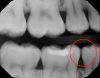

Fig 3. Caries confirmed through use of transillumination.

Figure 3

Figure 1 shows a pretreatment photograph of a tooth No. 20. In Figure 2, the circled area of the x-ray indicates the interproximal area where the clinician was uncertain if caries was present. Though x-rays are useful, transillumination is more sensitive and optimal for detecting caries in the early stages.12 With new devices, clinicians can acquire more information before working on the tooth. As shown in Figure 3, caries was confirmed using the transillumination system (CariVu), though it did not show up on an x-ray. The clinician was able to show the image to the patient. The open-tooth camera image then revealed the extent of the caries in the exact position that was displayed in the transillumination image (Figure 4). This is a significant advantage in minimizing preparations and saving valuable tooth structure.